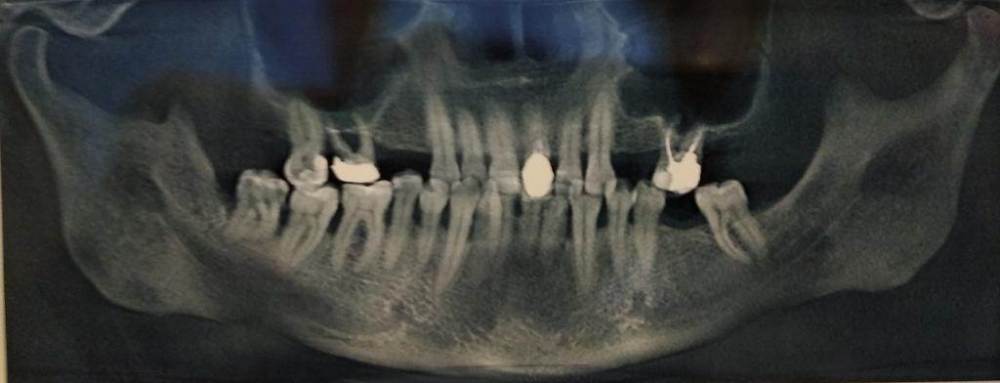

Vldmr28 Опубликовано 26 ноября, 2022 Поделиться Опубликовано 26 ноября, 2022 Добрый день, хотелось бы узнать мнение специалистов по следующей проблеме - планируется установка имплантов на верхней челюсти: с обеих сторон отсутствуют 4,5, 6 с обеих сторона на удаление (кариес корня вроде бы), на одной стороне есть 7. Был на консультациях у двух специалистов. Планы лечения примерно совпадают: сначала синус-лифтинг, затем имплантация. Но в одном случае рекомендовано 6 имплантов - 6 коронок, в другом рекомендовано 4 импланта и два мостовидных протеза с опорами на 4 и 6. Второй вариант экономически выгоднее, но хотелось бы уяснить для себя - насколько надежен. Из дополнительной информации о сопутствующих заболеваниях – в 2013 году перенесён инфаркт миокарда, установлен стент. Принимаю статины, бисопролол, рамиприл, кардиомагнил. Анализы сдаю периодически, на данный момент результаты удовлетворительные. Ссылка на комментарий